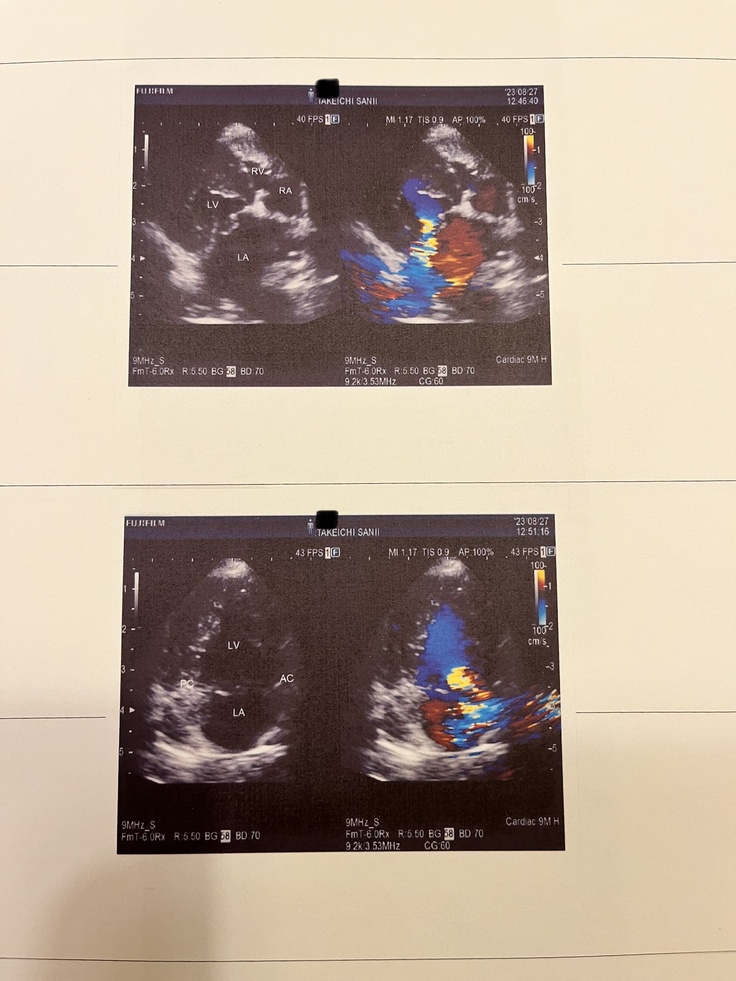

★僧帽弁閉鎖不全症

犬の僧帽弁閉鎖不全症は、心臓の左心房から左心室に流れる時に通過する僧帽弁に異常が起こる病気です。本来血液は左心房から左心室へ一方通行で流れ、僧帽弁がしっかり閉じることで逆流しない仕組みになっています。しかし僧帽弁がもろくなったり、切れてしまうと弁の閉鎖機能が悪くなり、血液の逆流が起こります。この病態を僧帽弁閉鎖不全症と呼びます。

ご紹介いただいた専門病院で検査をしていただくと、手術可能な状態であること、成功率は95%、症状から早めの手術をおすすめされました。